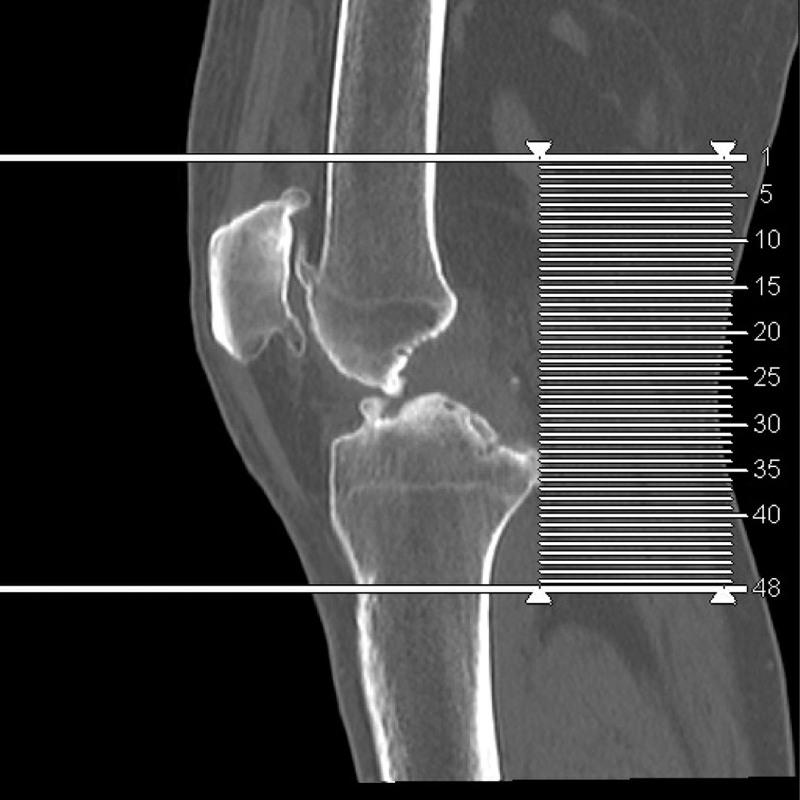

An elderly male aged 67, was admitted to the hospital for chronic pain in his left knee. An outpatient physical examination reveals a significantly thicker left lower limb accompanied by multiple varicose veins. The right lower limb was 2 cm short on the opposite side, and the right foot was stunted with high arch deformity. The entire body was covered in a red grape globus, which faded after pressing. He was diagnosed with KTS. We performed TKA for him after blood coagulation examination. The patient recovered well after the operation. He was followed up for 1 year, The patient is in good condition and satisfied with the operation.

一名 67 岁老年男性,因左膝慢性疼痛入院。门诊体检发现左下肢明显增粗,伴多发静脉曲张。对侧下肢短缩 2cm,右足发育不良,高弓畸形。全身布满红色葡萄样斑,按压后褪色。诊断为 KTS。行凝血检查后为他行 TKA。术后患者恢复良好。随访 1 年,患者情况良好,对手术满意。